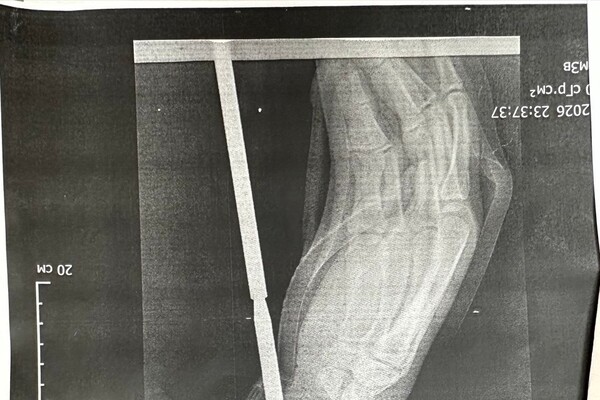

«Гарпун с двумя зубцами прошел между костями, не задев их. Специалисты извлекли инородное тело, обработали колотую рану и оказали пациенту квалифицированную помощь», — говорится в публикации.